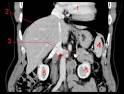

JFR La veine cave infrieure : cette grande mconnue

De la paroi veineuse par une tumeur ou par une thrombose. Thrombose cave suprieure de cause endoluminale ou paritale. Les trois T cave infrieurs : thrombose, tumeurs, traumatisme.